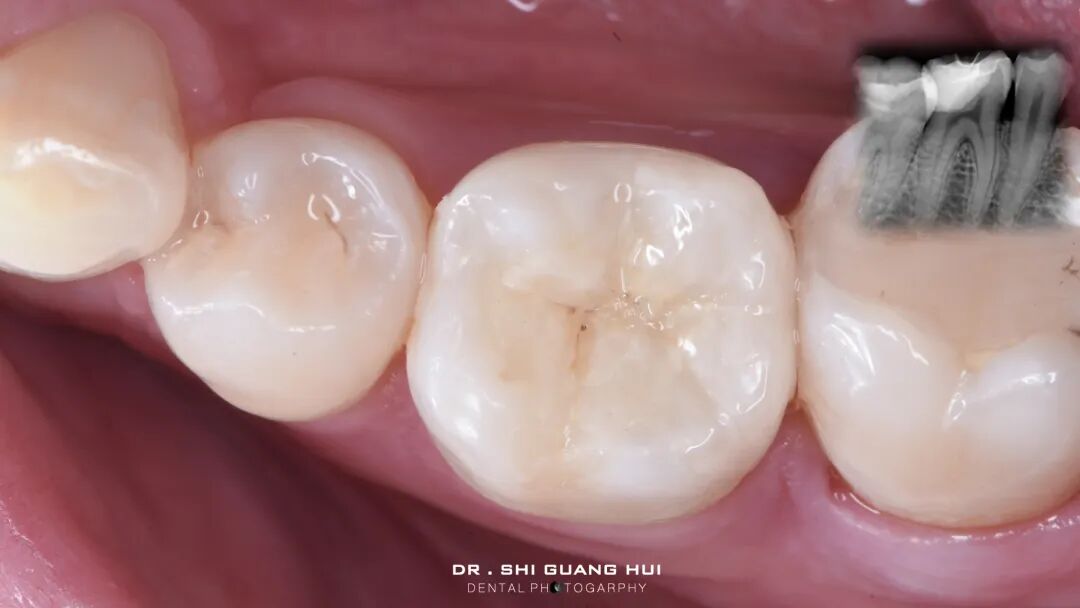

口腔检查:46远中邻面可见深大龋洞,窝洞内可见黑褐色腐质,质软,至牙本质深层。冷诊无明显反应。叩痛(-),牙髓活力测试正常。

辅助检查:46根尖未见异常。

诊断:46深龋

治疗方案:46嵌体修复

局部麻醉下进行去除腐质,可见远中邻面边缘位于龈下。由于近髓,剩余核心区域腐质橡皮障隔离后再进行去除。

橡皮障隔离患牙,去净腐质,然后进行详细的生物力学分析,远中舌尖无牙本质支撑,需要牙尖覆盖,降低1.5mm左右,远中颊尖厚度足够。近中邻面边缘嵴完整,远中邻面边缘需要进行CMR。